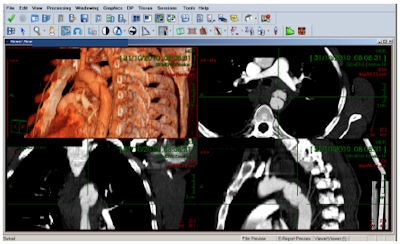

Using PACS, doctors were able to save the life of a 40-year-old patient following a road traffic accident. CT angiography at Meir Medical Center (level II trauma) demonstrated a contained traumatic rupture of the aorta — a life-threatening condition. Meir emergency room doctors consulted the cardiothoracic unit in Rabin Medical Center (level I trauma) using the PACS. Both groups were able to view in real-time the CT study containing 2,000 images (1,000 MB of imaging data). The advanced visualization tools embedded in the PACS made it possible to complete the diagnosis and surgical planning in minimal time. The images show maximal intensity projection (MIP) and volume rendering (VR) of the ruptured aorta.Clalit's system needed to incorporate other domains beyond cardiology and endoscopy, even factoring in pathology as a future target domain, according to Makori. Therefore, the PACS had to support multimedia, including JPEGs and movies, in addition to the DICOM standard for images, all of which needed to be seen in a centralized way.